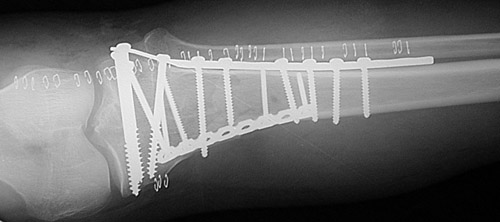

| The radiograph above reveals a highly comminuted spiral fracture of the proximal tibia with downward displacement of the tibial plateau. This was the result of a high speed vehicular accident. In the view below, the fracture has been stabilized with open reduction and internal fixation (ORIF). Staples close the incision. |